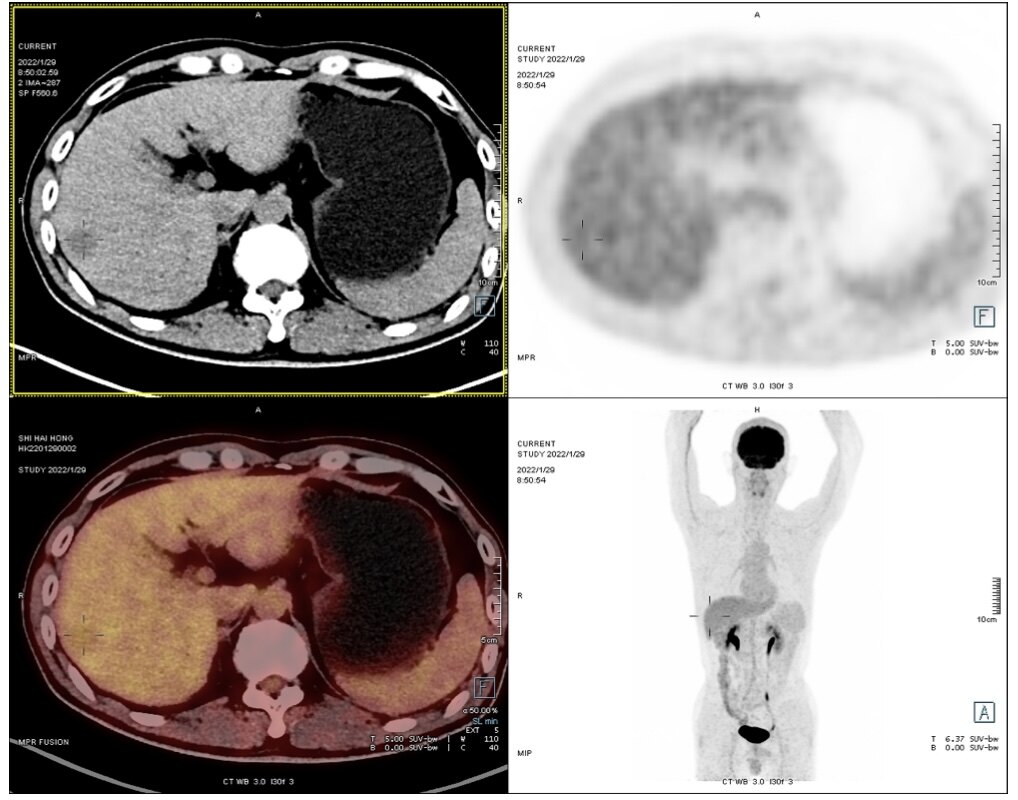

手术切除是早期肝癌安全(手术死亡率为0)、有效(5年生存率达到70%)、高性价比(报销前费用在3万元左右)的治疗方式。以下4例有乙肝病史,经定期筛查(肝脏B超和甲胎蛋白)发现的早期肝癌,手术切除后平均住院时间6天,无任何并发症,自费仅数千元。